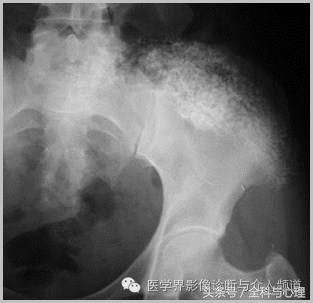

4、痛风石

为尿酸盐沉积形成,发生在关节周围软组织、包括韧带、肌腱、滑囊,眼、耳、鼻、喉、皮肤, 50%的钙化为X线平片可见。

痛风石,可见软组织肿胀及钙化灶。